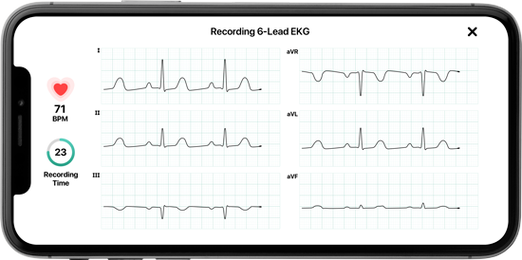

6 DERIVAZIONI

L’elettrocardiografo tascabile più piccolo e preciso al mondo. Con 2 sole dita un ECG ad 1 canale - con 2 dita+1 arto inferiore un ECG a 6 canali